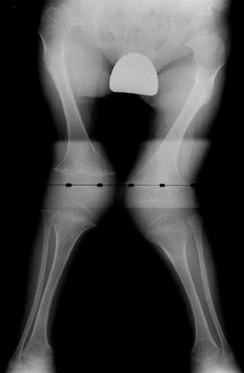

![]() |

|

Figure 180.8.

Radiograph of the lower extremities of a 4-year-old girl with metaphyseal chondrodysplasia. Genu varum and widened physes are seen. |